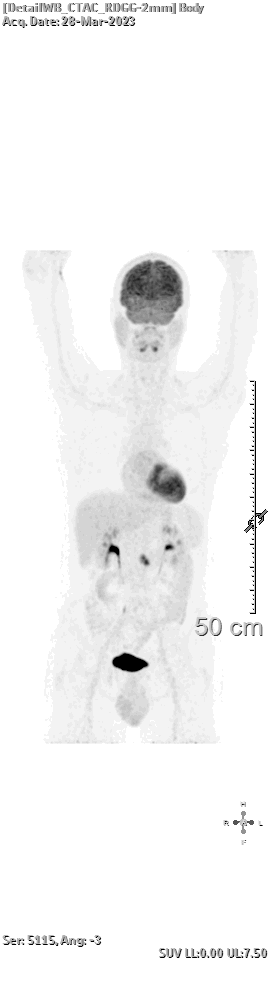

Wat dacht je van een totaal draaiende doorlichting van mijn lichaam, d.d. 28 maart 2023. Met handen boven het hoofd. Niet omdat ik bij de douane sta, maar omdat ik op de scan met mijn armen boven mijn hoofd moet liggen.

Ik heb er geen verstand van, maar op hoogte van de bovenkant van de ’50’ zit -zo denk ik- de tumor. Ongeveer 2 cm groot vlak naast het begin van mijn dunne darm.

(wat oplicht verbruikt glucose, hersenen, hart en nog wat organen… maar ook één stipje bij mijn darm dus)